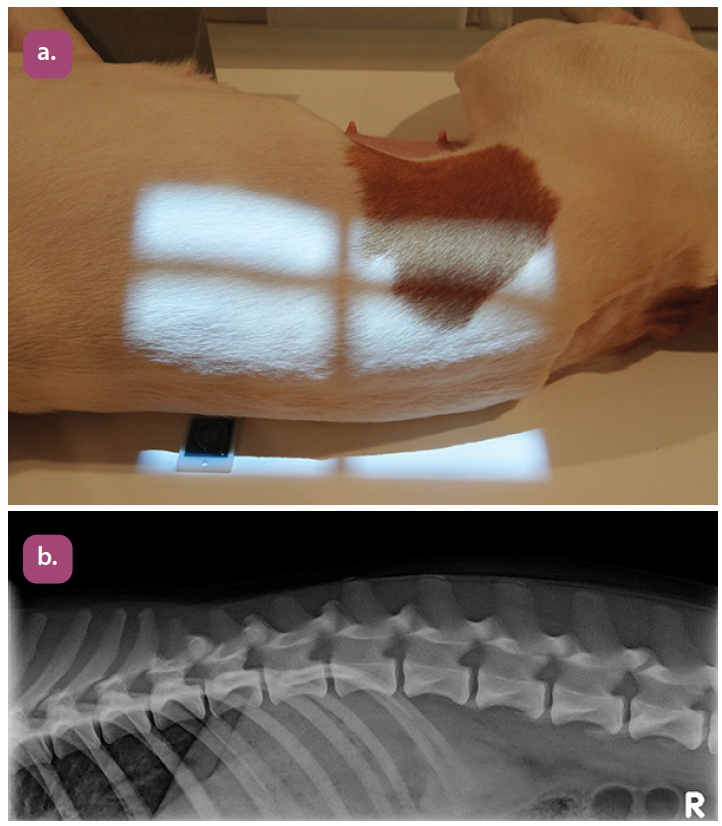

lateral thoracic spine projection

lateral thoracolumbar spine projection